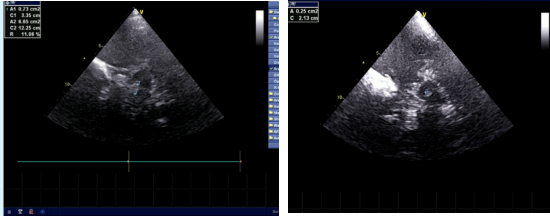

左图:正常黑质丨右图:黑质内高回声

黑质(substantia nigra, SN)是位于中脑的特殊结构,是调节运动的重要中枢。黑质是脑内合成多巴胺的主要核团,多巴胺也被称作“神奇的开心分子”;某些原因导致黑质细胞变性,造成多巴胺合成减少,这便是引起震颤麻痹的主要病因。

“脑黑质超声”检查,即超声探头通过颞窗直接扫查中脑黑质,了解黑质回声情况,为帕金森病的诊疗提供依据,具有无创、便捷、经济、可重复性高、患者检查中不必完全制动等优点。据悉,“脑黑质超声”是一项超声检查新技术,目前在区内外开展该检查技术仍然较少,对仪器要求较高,今后还要充分发挥该检查的临床价值,不断推广应用。

然而由于多数帕金森患者早期临床表现不典型,不易与其他帕金森综合征鉴别,近年来影像学的发展为帕金森的诊断及鉴别诊断提供了重要参考价值,包括CT、MRI、PET、经颅超声等,其中经颅超声具有安全简单、无创、费用低廉及重复性强的优点,使得经颅超声在临床上备受关注。被作为2016版《中国帕金森病诊断标准》的支持标准之一,目前已广泛应用于临床实践,能够对疑似PD患者进行早期鉴别诊断及早期筛选。